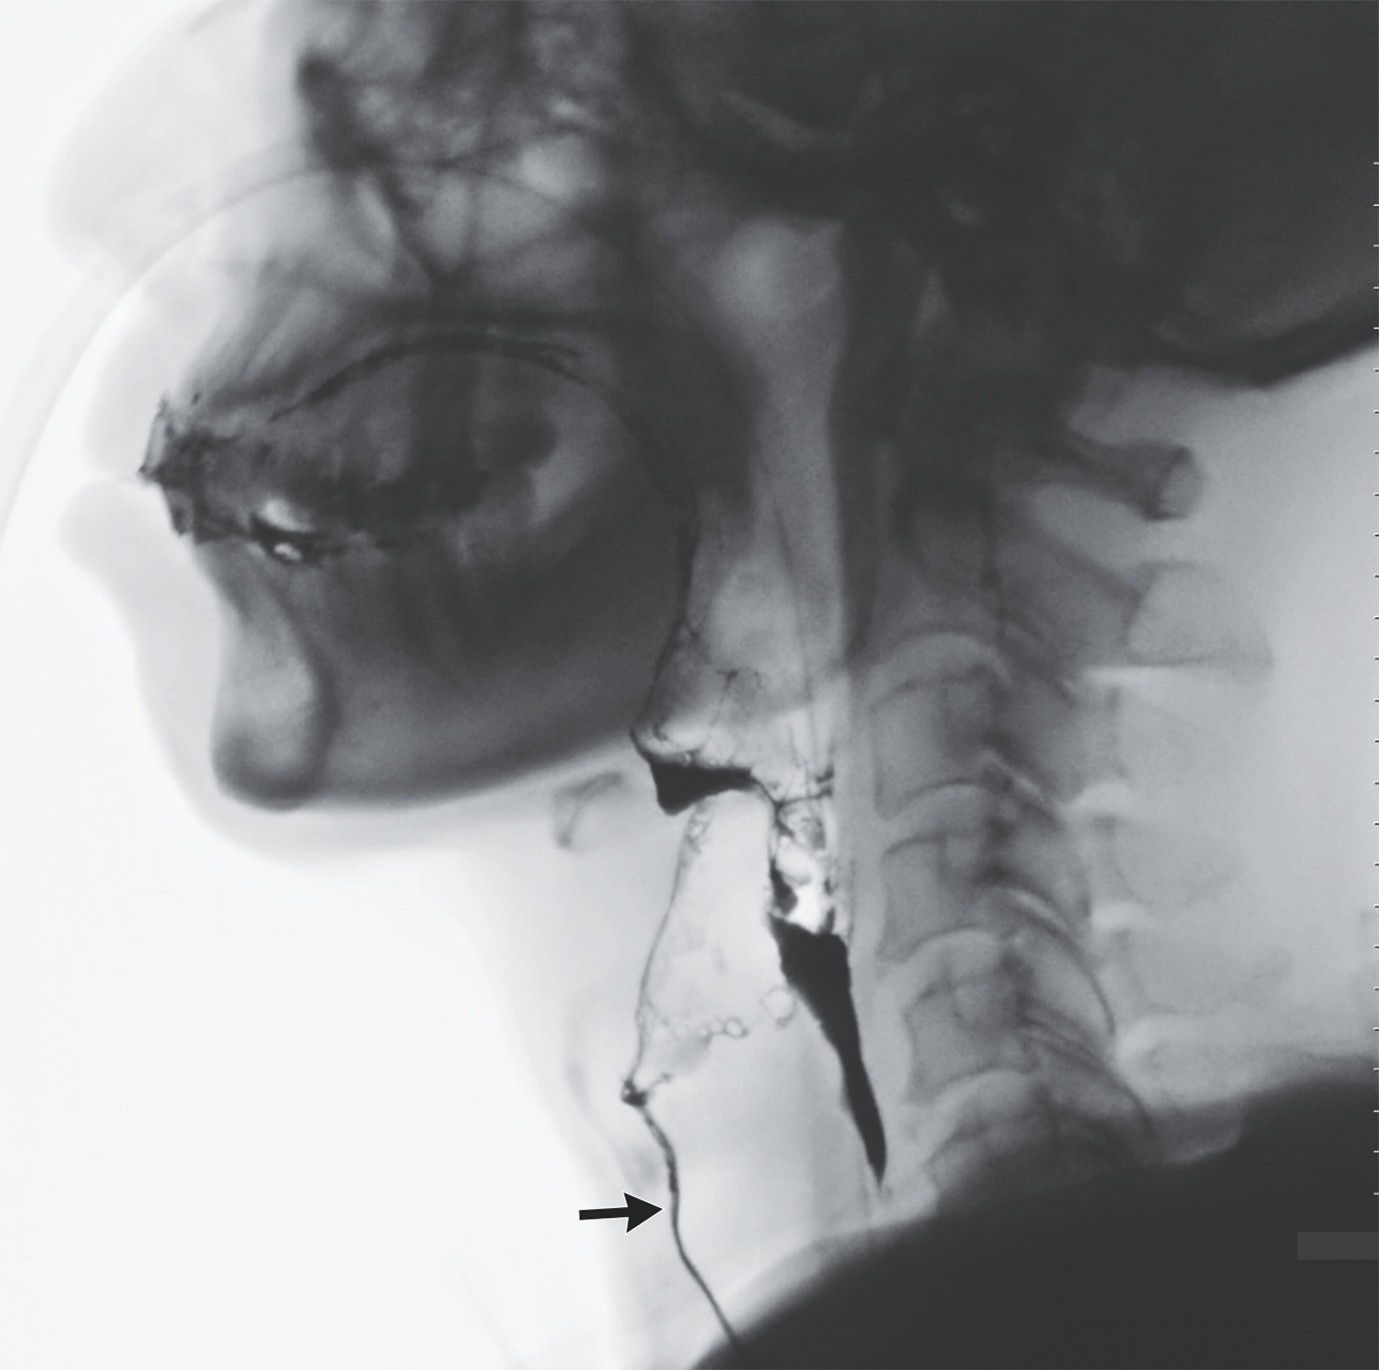

(4).Silent Aspiration

Shuo-Ting Jian, Published April 4, 2026,DOI: 10.1056/NEJMicm2516115

A 68-year-old man who had undergone intubation 25 days earlier had difficulty swallowing after extubation. A swallowing study showed fluid penetrating into the trachea without triggering a cough reflex